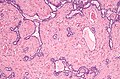

- Delicate anastomosing channels lined by cuboid epithelium.

Images